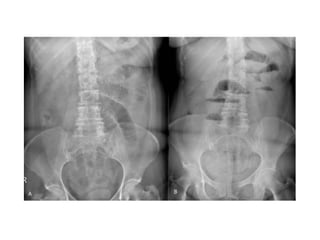

• La triada clásica de

obstrucción en el examen

radiológico es:

o Asas de intestino delgado dilatadas

(mayores a 3 cm)

o Niveles hidroaéreos

o Ausencia de aire distal

Signo del “grano de café”

Hallazgo clásico y diagnóstico del vólvulo sigmoideo en una radiografía simple de abdomen

El diagnóstico seconfirma mediante estudios radiológicos SERIE ABDOMINAL Rx abdomen paciente en posición supina Rx tórax Rx abdomen con enfermo de pie SENSIBILIDAD DEL 70 AL 80%

• La triadaclásica de obstrucción en el examen radiológico es: o Asas de intestino delgado dilatadas (mayores a 3 cm) o Niveles hidroaéreos o Ausencia de aire distal

Signo del “granode café” Hallazgo clásico y diagnóstico del vólvulo sigmoideo en una radiografía simple de abdomen